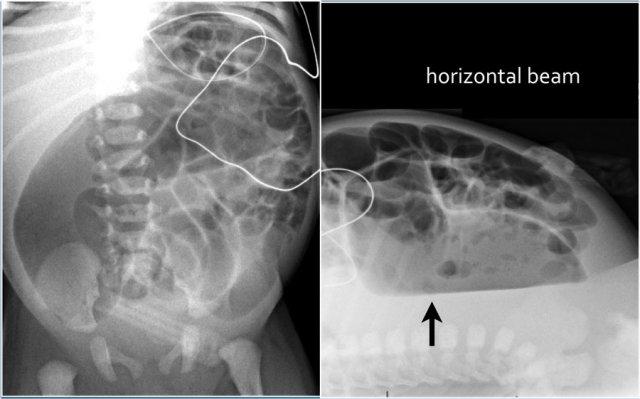

Hãy quan sát hình ảnh.

Các dấu hiệu là gì?

Sau đó cuộn sang hình ảnh tiếp theo.

Nhận xét:

- Điều trông giống như phân dạng hạt trong lòng ruột (mũi tên vàng) thực chất là do khí trong thành ruột nhìn theo hướng trực diện (en face).

- Khí trong thành ruột dễ nhận biết nhất khi nhìn theo hướng tiếp tuyến, biểu hiện là các đường đen tuyến tính song song với lòng ruột (mũi tên xanh lá).

Khí trong thành ruột (Pneumatosis intestinalis) được định nghĩa là sự hiện diện của khí trong thành ruột.

Ở trẻ sơ sinh, dấu hiệu này gặp trong thiếu máu thành ruột do viêm ruột hoại tử.

Trên phim X-quang, khí trong thành ruột trông giống như phân dạng hạt, vốn là hình ảnh bình thường ở trẻ lớn hơn.

Tuy nhiên, trẻ sơ sinh chưa có phân dạng hạt vì chúng chỉ bú sữa.

Do đó, hình ảnh trông giống phân dạng hạt trong lòng ruột thực chất là khí trong thành ruột.

Các bóng khí có thể được hấp thu vào hệ thống tĩnh mạch, gây ra khí trong tĩnh mạch cửa.

Khí trong thành ruột có thể dẫn đến thủng ruột, biểu hiện là khí tự do trong ổ bụng (pneumoperitoneum).